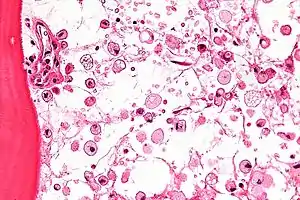

The disease is caused by a defect in the housekeeping gene for lysosomal glucocerebrosidase (also known as beta-glucosidase, EC 3.2.1.45, PDB: 1OGS) on the first chromosome (1q22). The enzyme is a 55.6-kilodalton, 497-amino acid-long protein that catalyses the breakdown of glucocerebroside, a cell membrane constituent of red and white blood cells. In Gaucher disease, the enzyme is unable to function correctly and glucocerebroside accumulates. The macrophages that clear these cells are unable to eliminate the waste product, which accumulates in fibrils, and turn into 'Gaucher cells', which appear on light microscopy to resemble crumpled-up paper.[3]

A diagnosis can also be implied by biochemical abnormalities such as high alkaline phosphatase, angiotensin-converting enzyme, and immunoglobulin levels, or by cell analysis showing "crinkled paper" cytoplasm and glycolipid-laden macrophages.